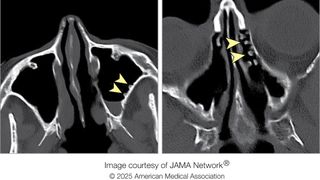

Cold-water rinses left 'cobblestone' growths in woman's sinuses

By Mindy Weisberger published

A woman developed prominent bumps inside her sinuses, similar to a condition seen in "surfer's ear."